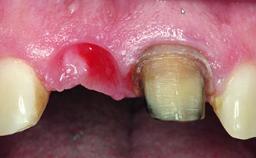

Replacement of an Ankylosed Upper Left Central Incisor: Bone Augmentation and Socket Grafting, Late Placement of an RC Bone Level Implant

A 15-year-old male patient was referred to us by his pediatric dentist in June 2004 for evaluation of treatment options for his failing tooth 21. The patient had recently seen an endodontist for internal bleaching and been advised that there had been significant resorption and ankylosis. The patient’s mother was concerned because the tooth appeared shorter than the adjacent one. His past dental history was significant for trauma (September 2001), where the tooth had been avulsed and reimplanted. Teeth 11 and 21 had been endodontically treated.